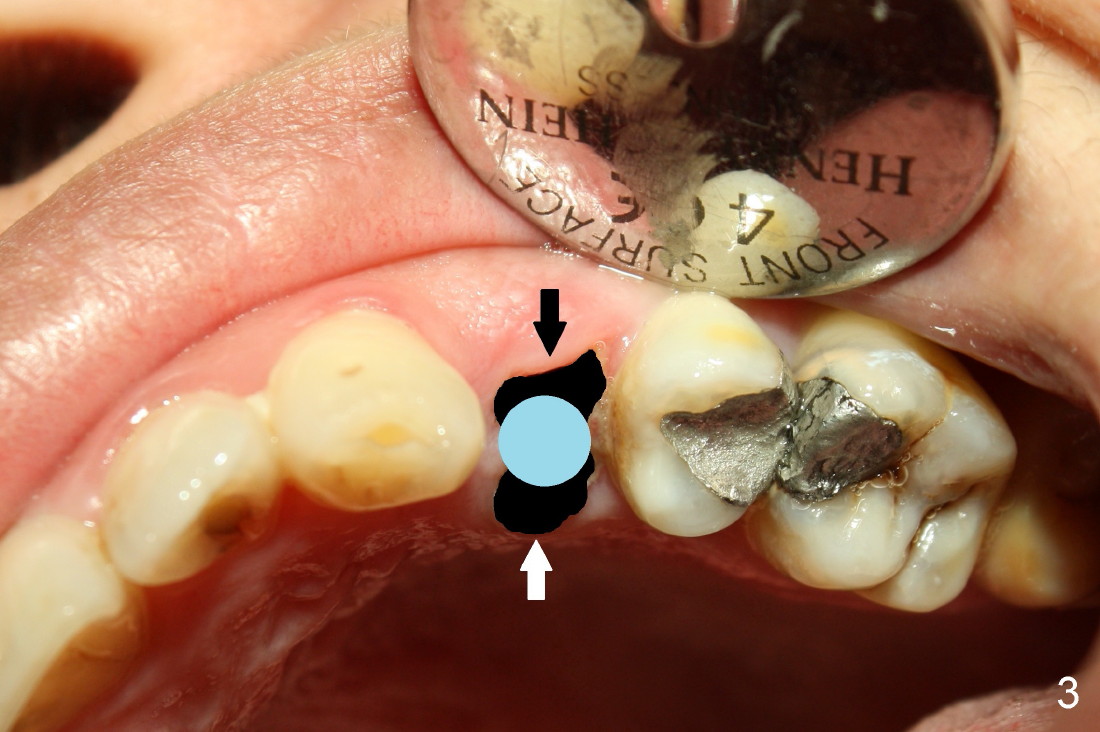

Fig.2 (occlusal view) shows the oval socket (buccolingual width vs. the mesiodistal one). It appears that when a rounded implant is placed, the buccal and lingual flaps should be raised and and advanced to close the socket (Fig.3).